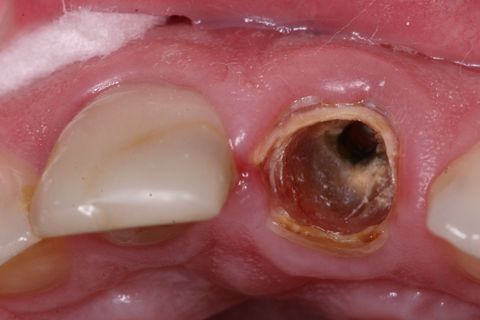

Aspecto clínico inicial (vista oclusal)

Paciente jovem do gênero masculino, apresentou-se à Clínica Integrada do Curso de Odontologia da Universidade Severino Sombra necessitando de um tratamento restaurador no dente 21. Ao exame clínico e radiográfico foi observado uma grande destruição coronária e tratamento endodontico satisfatório (Figuras 1, 2 e 3).